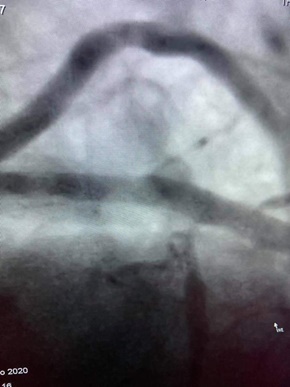

Λαμβάνοντας υπόψη ότι ο ασθενής δεν παρουσίαζε συμπτωματολογία από το κεντρικό νευρικό σύστημα, πραγματοποιήθηκε από τον αγγειοχειρουργό κ. Νεκτάριο Γαλάνη χειρουργική προσπέλαση από την βραχιόνιο αρτηρία και σε συνεργασία με τον κ. Μαγκούτη, επιτυχής αγγειοπλαστική με μπαλόνι της αριστερής μασχαλιαίας και υποκλειδίου αρτηρίας και στη συνέχεια στεφανιογραφία, η οποία ανέδειξε υφολική απόφραξη του προσθίου κατιόντα. Στον ίδιο χρόνο, πραγματοποιήθηκε επιτυχής αγγειοπλαστική από τον κ. Μαγκούτη με πλήρη αποκατάσταση των στενώσεων. Ο ασθενής εξήλθε μέσα σε 24 ώρες.

[bt_columns] [bt_column class="bt-column col-xs-12 col-sm-12 col-md-6 col-lg-6 center"]Πριν την αγγειοπλαστική

Πριν την αγγειοπλαστική[/bt_column] [bt_column class="bt-column col-xs-12 col-sm-12 col-md-6 col-lg-6 center"]Μετά την αγγειοπλαστική

Μετά την αγγειοπλαστική[/bt_column] [/bt_columns]